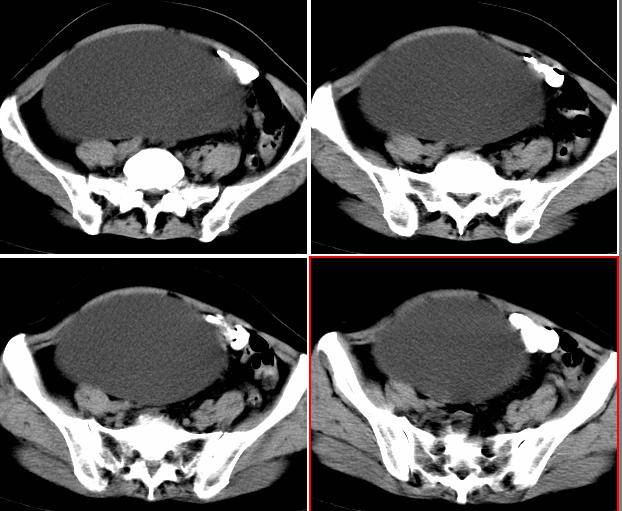

从囊性低密度区的形态,及分布看我支持1楼战友的分析及诊断意见。{右恻输尿管全程扩张,阻塞位置应该在输尿管与膀胱的交界区,建议行膀胱镜检,楼主还是应该给患者作强化扫描!!!!!}

右侧巨大囊状无功能肾,输尿管积水(输尿管梗阻所致)。

右输尿管肾盂肾盏高度括张扭曲,第三狭窄处或周围应见结石或其他原因梗阻。考虑先天畸型,如重复畸形。

右肾明显扩大,皮质菲薄,间隔细,右输尿管全程扩张,右肾重度积水,原因应重点查输尿管膀胱接合处。

右侧巨大囊状无功能肾,输尿管积水.右侧积水肾旁囊性病灶应该是左侧卵巢浆液性囊腺瘤.